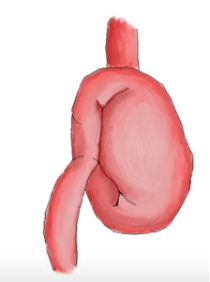

Direction of gastric volvulus

What is mesenteroaxial?